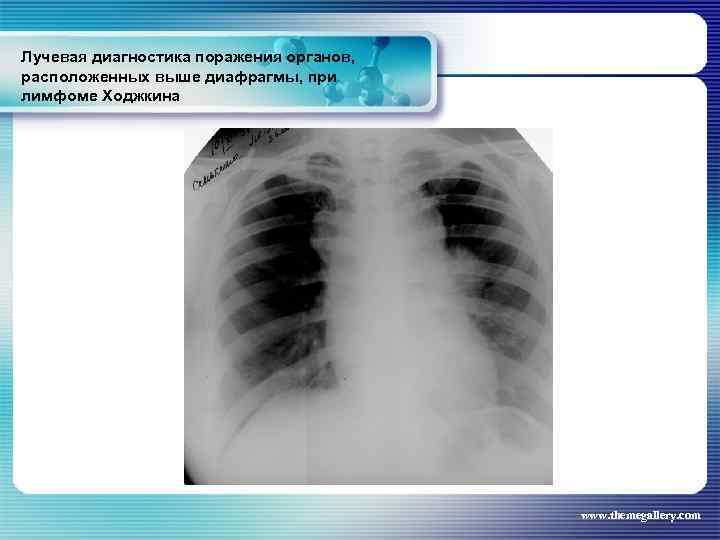

Лучевая диагностика поражения органов, расположенных выше диафрагмы, при лимфоме Ходжкина Частота поражения органов грудной полости при лимфоме Ходжкина: поражение средостения легких плевры грудной стенки - 66, 7 % 33, 75% 5, 3% 1, 8% www. themegallery. com

Лучевая диагностика поражения органов, расположенных выше диафрагмы, при лимфоме Ходжкина Частота поражения органов грудной полости при лимфоме Ходжкина: поражение средостения легких плевры грудной стенки - 66, 7 % 33, 75% 5, 3% 1, 8% www. themegallery. com

Лучевая диагностика поражения органов, расположенных выше диафрагмы, при лимфоме Ходжкина www. themegallery. com

Лучевая диагностика поражения органов, расположенных выше диафрагмы, при лимфоме Ходжкина www. themegallery. com